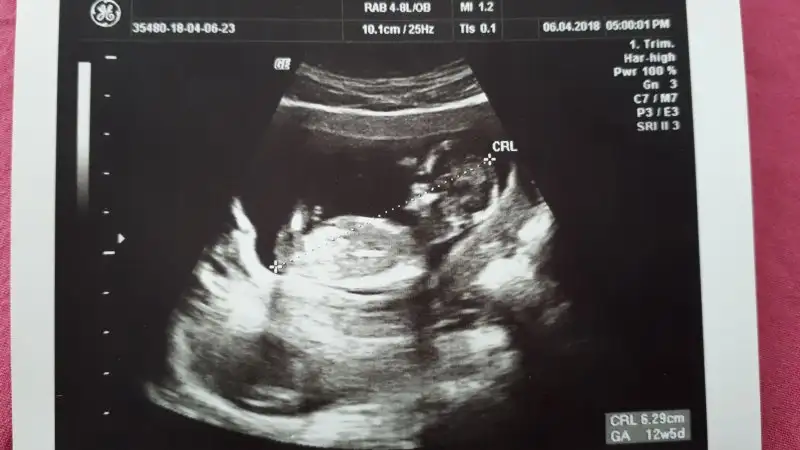

Arkadaslar lutfen yorumlayin ya sizce ne cinsiyeti 12+5 haftalik burada

Eklentiler

• IMG-20180407-WA0002.webp

IMG-20180407-WA0002.webp

18,8 KB · Görüntüleme: 137